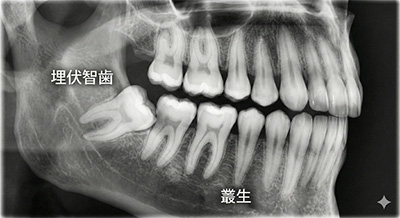

親知らずの多くは、斜めに生えていたり、埋まっていたりと、きれいに生えていません。

中には、奥歯を前に向かって押そうとする向きに生えてくるケースもあります。もし手前の奥歯を前に押し出すと、全体的な歯並びのバランスも崩れてしまいます。すると、噛み合わせが悪くなり、顎関節症になるというわけです。また、それほど多くはありませんが、親知らずを抜いた後に顎関節症になることもあります。